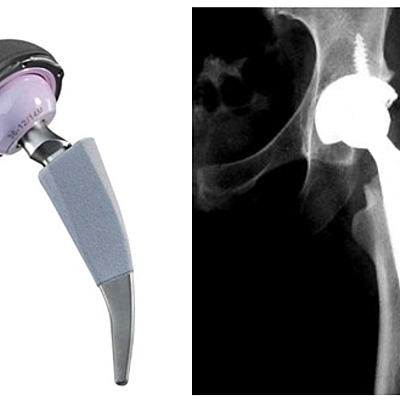

Reemplazo de cadera y abordajes